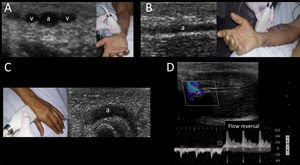

Radial arteryRadial artery emerges from bifurcation of the brachial artery at the elbow crease and is found in the lateral side of the distal forearm near the wrist, where it becomes more superficial and easier to palpate. Accordingly, this artery is usually well recognized by US and accessed from its distal ventral and more superficial segment. This vessel is accompanied by the paired radial veins, located at both sides of the artery (Supplementary material, Fig. 9A and B). Applying a tourniquet distal to the site of cannulation has been shown to improve the arterial dimensions and thus this maneuver can be considered in practice when the artery is too small.26

Additionally, the radial artery can be recognized and cannulated using US in its dorsal segment, found in the anatomical snuffbox (Supplementary material, Fig. 9C). This can be considered as a valid alternative when the more proximal radial artery cannot be accessed.27

Pooled data analysis showed a 36% reduction in the rate of catheterization failure at the first attempt and an 83% reduction in the number of hematomas; however, overall success rate is not reported. Despite this, benefits outweigh risks and thus US-guided radial insertion is probably recommended over the traditional technique.18

The permeability of the palmar arch must be assessed prior to cannulating this artery. This can be performed using the modified Allen test, plethysmographic Allen test28 or modified duplex Allen test.29 The last one is done placing the transducer in the anatomical snuffbox and identifying the radial artery flow by color and spectral Doppler. After spectral waveforms are obtained, the radial artery is compressed proximal to the site of insonation. Normally, reversal of flow confirms patency of the deep palmar arch (Supplementary material, Fig. 9D). Otherwise, an inadequate deep palmar arch is suspected and thus this artery is best avoided for cannulation.